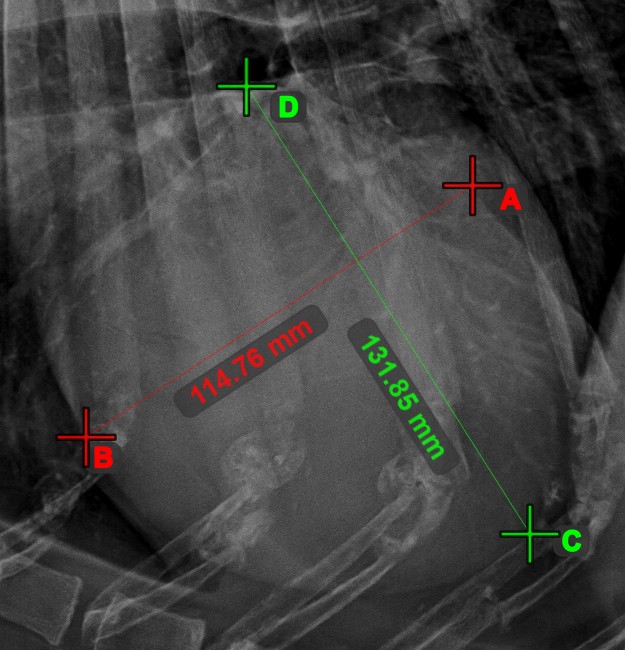

Line Intersection¶

Quickly and accurately locate and mark the intersection point between two existing lines by using the Line Intersection tool.

Select the tool from the left toolbar and assign it to one of the available mouse buttons. Select two lines that have already been drawn on the scene to complete the measurement. The intersection point of the line will be automatically calculated and marked on the scene. The intersection point of two lines will always be marked with the letter X.

Information

If two lines do not intersect directly, the intersection point of their extended projections on the scene will be marked.